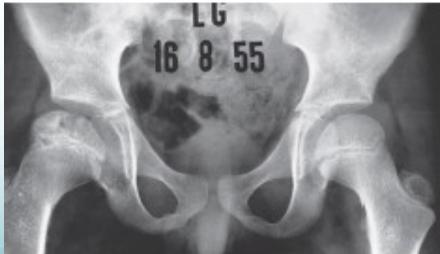

Radiological Progression:

Progression: Sclerosis → Collapse → Fragmentation → Remodeling

Imaging Examples: